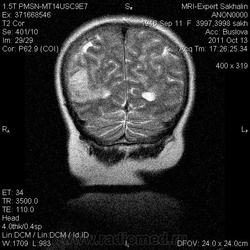

Ишемический инфаркт

ОНМК по ишемическому типу в бассейне правой СМА. Судя по очагам накопления в коре, подострое.

Последствия ОНМК с геморрагическим пропитыванием справа. Кистозно-атрофические изменения в левой гемисфере мозжечка (последствия ОНМК ). Множественные очаги сливного характера вещества головного мозга ( поля лейкоариоза)

Да хотела еще добавить возможно у пациента еще были лакунарные инсульты. В области базальных ядер( слева ) определяются кисты, окруженные глиозом. И на предпоследнем изображение в правой гемисфере мозжечка по- моему и также есть нмк.

Танюша, все указала-и лакунаные постишемические кисты, и кистозно-глиозные левой гемисферы мозжечка.Правая , вроде бы, не задействована в процессе.